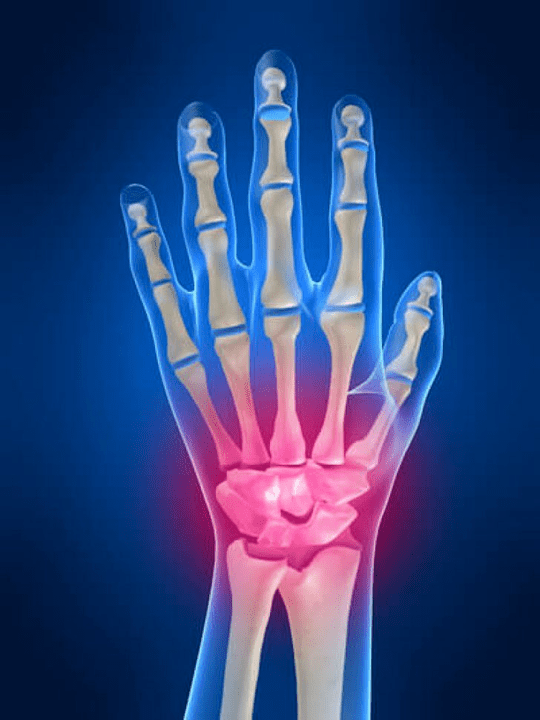

Locītavu sāpes Pirksti ir neaizstājama pazīme par jebkuru kopīgu patoloģiju, kurā ir bojāti šo savienojumu strukturālās sastāvdaļas. Pirmkārt, sāpes šo locītavu apgabalā var būt saistītas ar dažādām autoimūnām slimībām (Sistēmiski sarkans spīdums, reimatoīdais artrīts, psoriātiskais artrīts utt.) kurā imūnie faktori nodara kaitējumu viņu pašu locītavu audiem.

Nākamais galvenais iemesls, kas var sākt sāpināt Pirkstu locītavās var būt ievainojumi (sasitumi, dislokācijas, kaulu lūzumi, saites). Sāpīgumu šajās locītavās var arī provocēt ar deģeneratīvām izmaiņām, kas notiek to locītavu audos. To bieži var novērot ar osteoartrītu.

Kādas struktūras var kļūt iekaisušas roku locītavās?

Iekaisums ir tipisks patoloģisks process, kas raksturīgs tiem audiem un orgāniem, kas tika bojāti jebkāda iemesla dēļ. Ir vērts atcerēties, ka vairumā gadījumu katra slimība (Piemēram, podagra, reimatoīdais artrīts utt.) vai trauma, kas vienā vai otrā pakāpē sabojā roku locītavas, ietekmē ne tikai locītavu, bet arī periosteru (nervi, muskuļi, cīpslas, zemādas tauki, āda) struktūras.

Šādas locītavu struktūras var kļūt iekaisušas roku locītavās:

- kopīgais skrimšļa;

- Kaulu audu saspiešana;

- locītavas kapsula;

- Locītavas saites.

Sāpju cēloņi rokas un pirkstu locītavās

Galvenā daļa starp iemesliem, kas izraisa sāpes rokas un pirkstu locītavās, aizņem ar mehāniskiem ievainojumiem (Lūzumi, dislokācijas, sasitumi utt.) un sistēmiskas autoimūnas slimības (Reimatoīdais artrīts, sistēmiska sarkanā vilkēde, psoriāze utt.). Papildus šiem cēloņiem, sāpīgums roku locītavās var izraisīt slimības, kas saistītas ar vielmaiņas traucējumiem (Piemēram, podagra, osteoartroze).